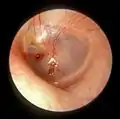

Rupture

Unintentional perforation (rupture) has been described in blast injuries[9] and air travel, typically in patients experiencing upper respiratory congestion or general Eustachian tube dysfunction that prevents equalization of pressure in the middle ear.[10] It is also known to occur in swimming, diving (including scuba diving),[11] and martial arts.[12]

Patients with tympanic membrane rupture may experience bleeding, tinnitus, hearing loss, or disequilibrium (vertigo). However, they rarely require medical intervention, as between 80 and 95 percent of ruptures recover completely within two to four weeks.[13][14][15] The prognosis becomes more guarded as the force of injury increases.[15]

In some cases, the pressure of fluid in an infected middle ear is great enough to cause the eardrum to rupture naturally. Usually, this consists of a small hole (perforation), from which fluid can drain of the middle ear. If this does not occur naturally, a myringotomy (tympanotomy, tympanostomy) can be performed. A myringotomy is a surgical procedure in which a tiny incision is created in the eardrum to relieve pressure caused by excessive buildup of fluid, or to drain pus from the middle ear. The fluid or pus comes from a middle ear infection (otitis media), which is a common problem in children. A tympanostomy tube is inserted into the eardrum to keep the middle ear aerated for a prolonged time and to prevent reaccumulation of fluid. Without the insertion of a tube, the incision usually heals spontaneously in two to three weeks. Depending on the type, the tube is either naturally extruded in 6 to 12 months or removed during a minor procedure.[16]